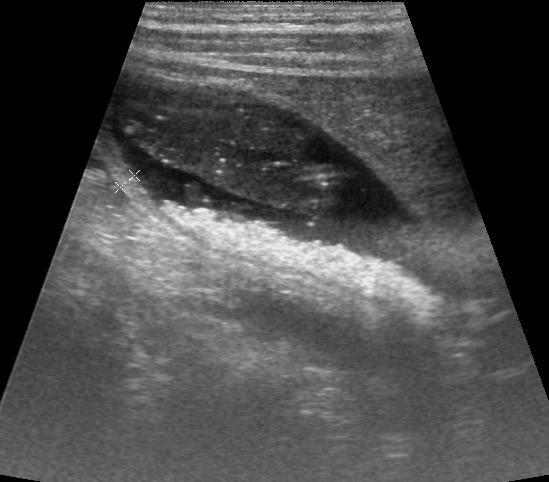

Большое спасибо за интересное сообщение, сегодня смотрела пациента, который лечится от пневмонии цефалоспоринами- псевдолитиаз.Я не поленилась, сходила в отделение и посмотрела амб.карту камней еще 1мес назад не было.